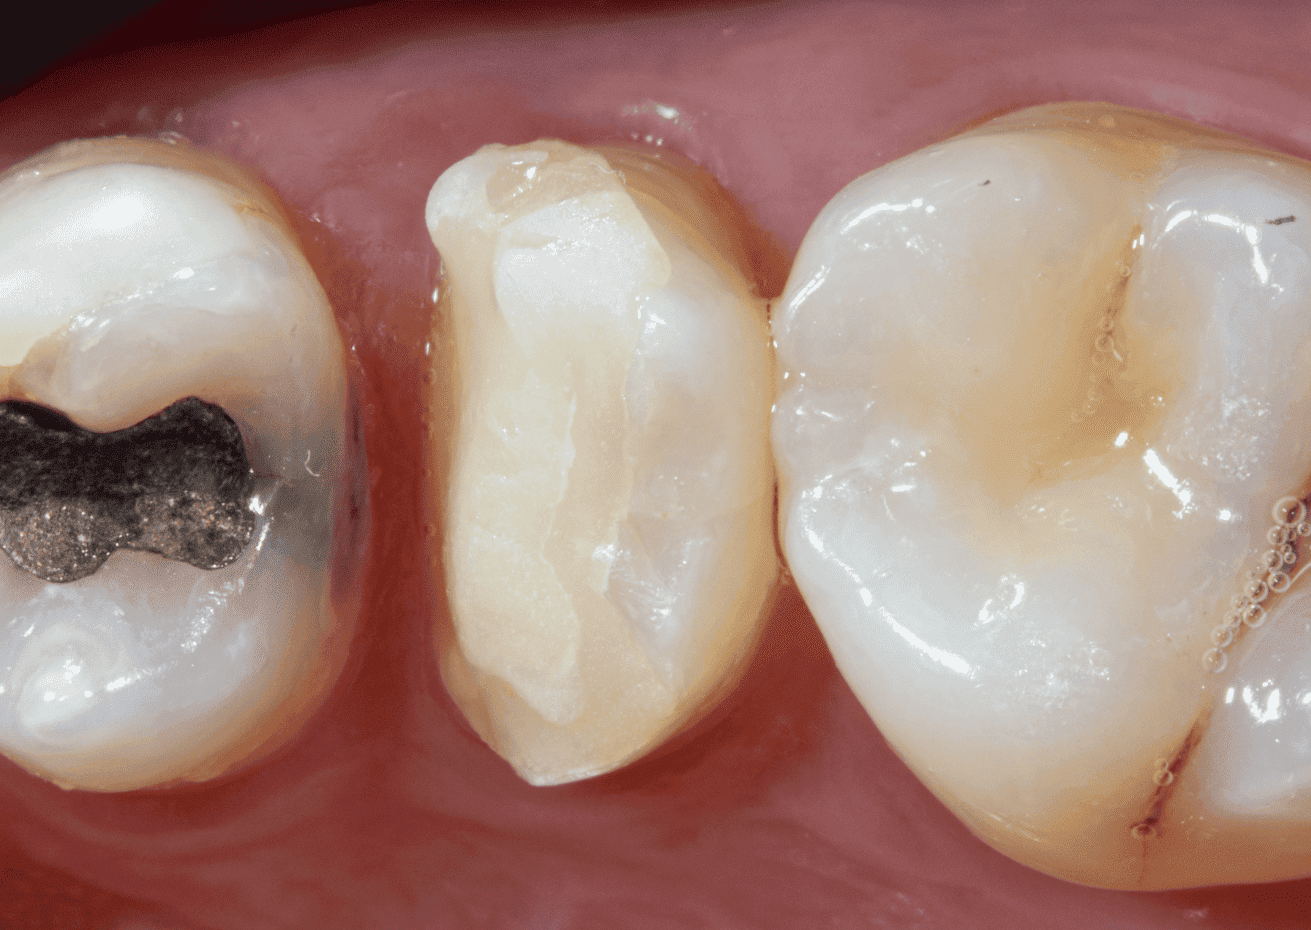

Paciente apresentou-se com elemento 15 com a necessidade de reabilitação protética devido a extensa perda de estrutura dentária.

O exame clínico inicial, do dente 15, apresentava selamento provisório com ionômero de vidro e exame radiográfico apresentava alívio de 2/3 do conduto.